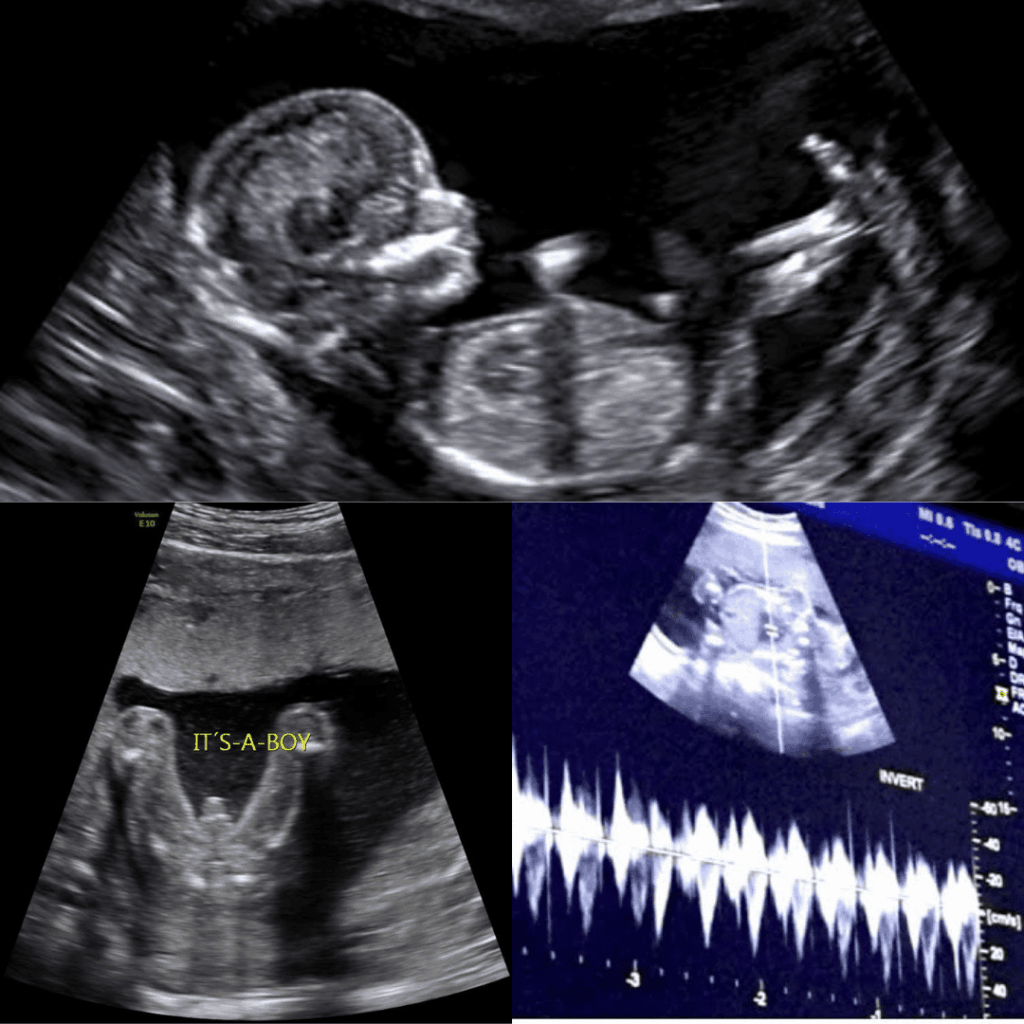

A 2D anatomy scan, also known as a fetal anatomy scan or level II ultrasound, is a detailed examination that focuses on assessing the anatomy and development of your baby. Using two-dimensional ultrasound technology, this scan provides a comprehensive view of your baby’s organs, limbs, and other structures, ensuring that they are developing properly.

The optimal time for a 2D anatomy scan is typically between 20 to 24 weeks of pregnancy. During this period, your baby’s anatomy is sufficiently developed for accurate assessment, and any potential abnormalities can be detected early, allowing for timely interventions if necessary.

7. Can a 2D anatomy scan determine the gender of my baby?

While the primary purpose of a 2D anatomy scan is to assess fetal anatomy, it may also reveal the gender of your baby if desired.